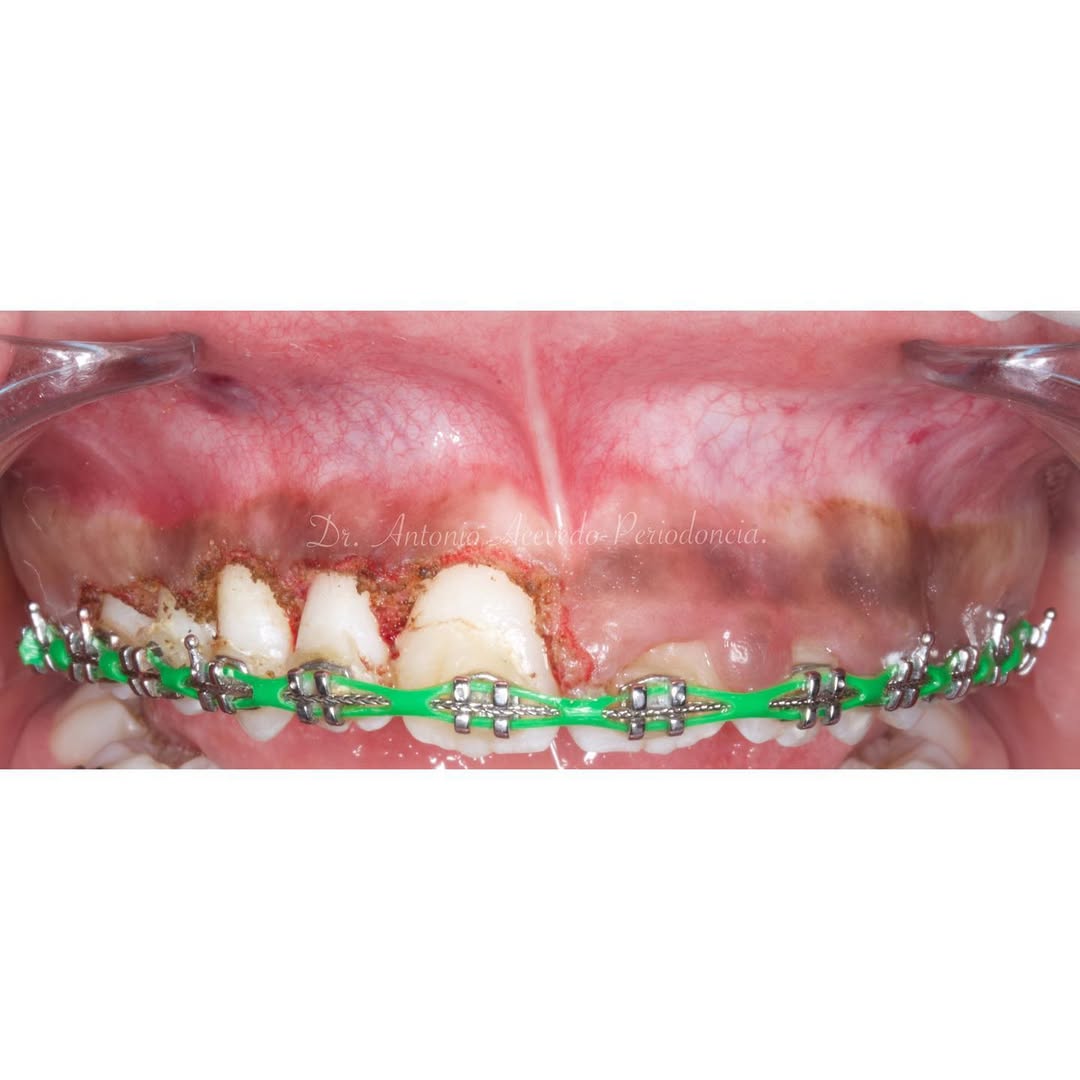

Se presenta un caso clínico de restauración directa en resina composite, ejemplo del valor de la precisión y la técnica meticulosa incluso en procedimientos considerados rutinarios dentro de la práctica diaria. El caso pone en evidencia la importancia del control de la morfología, la textura y la integración cromática, así como del adecuado aislamiento del campo operatorio y la estratificación del material, factores determinantes para conseguir un resultado natural, funcional y duradero. A través de una ejecución cuidadosa, se logró una restauración estéticamente imperceptible y funcionalmente estable, que respeta los principios de mínima invasión y adhesión efectiva. Este tipo de procedimientos, aunque cotidianos, reflejan la constancia y el nivel de exigencia clínica necesarios para ofrecer odontología de calidad en todos los casos, independientemente de su complejidad.

Hoy en día la Periodoncia es una de las áreas más importantes de la Odontología. En nuestro Centro de Formación te brindamos las mejores herramientas educativas y de capacitación necesarias para obtener el mayor provecho en el campo de la Odontología Estética y Restaurativa.

El objetivo del

Los problemas estéticos de una sonrisa no se ciñen sólo a los dientes eso lo sabemos todos. Por eso un curso de Perio-Estética, es fundamental para poder abordar casos de Estética y solo a través de un correcto diagnóstico previo podremos realizar un adecuado plan de tratamiento, muchas